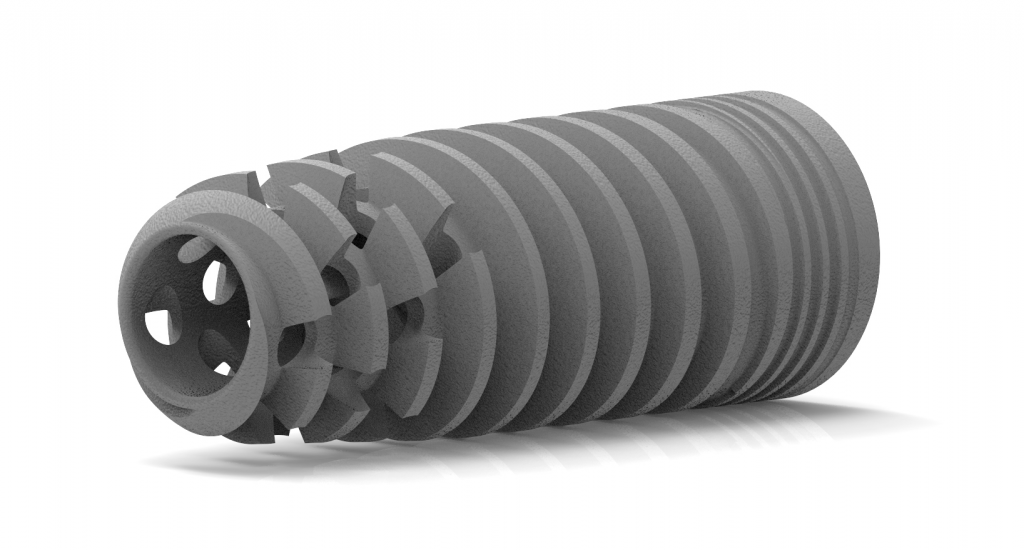

Desde 1985 tenho colaborado com o professor Per-Ingvar Brånemark e nos últimos anos, desenvolvi, juntamente com ele e Christian Brånemark, uma nova macro geometria do ápice do implante. Está parte apical do implante tem a função de reduzir o atrito, devido a seu corte preciso, controlando o torque de inserção, coletando lascas de tecido ósseo para o interior da câmara apical.

“Since 1985 I have been collaborating with professor Per-Ingvar Brånemark and during the last years, I have, together with him and Christian Brånemark, developed a new implant tip.This part of the implant is reducing friction, due to precise cutting, reducing insertion torque and collecting bone chips inside the tip part of”